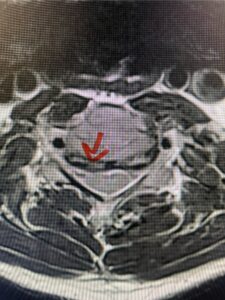

In this next case, this patient is a 47 year-old female who presents with intractable low back pain with severe pain, numbness, and weakness in the right lower extremity that had gotten progressively worse over a year. The patient had failed conservative management including physical therapy and epidurals. She was noted to have ⅘ weakness of plantar flexion. MRI demonstrated a large right L5-S1 disc herniation with severe compression of the descending right S1 nerve root (Fig 3). It was decided to perform a right L5-S1 hemilaminectomy for removal of the disc fragment and decompress the S1 nerve root. When you expose the disc, one must be certain to release any anterior adhesions to the nerve root in order to prevent a dural tear during retraction of the nerve root. It is also important to make sure during exposure and you finally encounter the dura after removing the ligamentum and fat, to make sure you are looking at the nerve root and not the main trunk of the thecal sac because if you don’t you can avulse or damage the nerve root if you retract the wrong structure.

Fig. 3a: Sagittal and axial T2-weighted lumbar MRI images demonstrating large right L5-S1 disc herniation (red arrows)